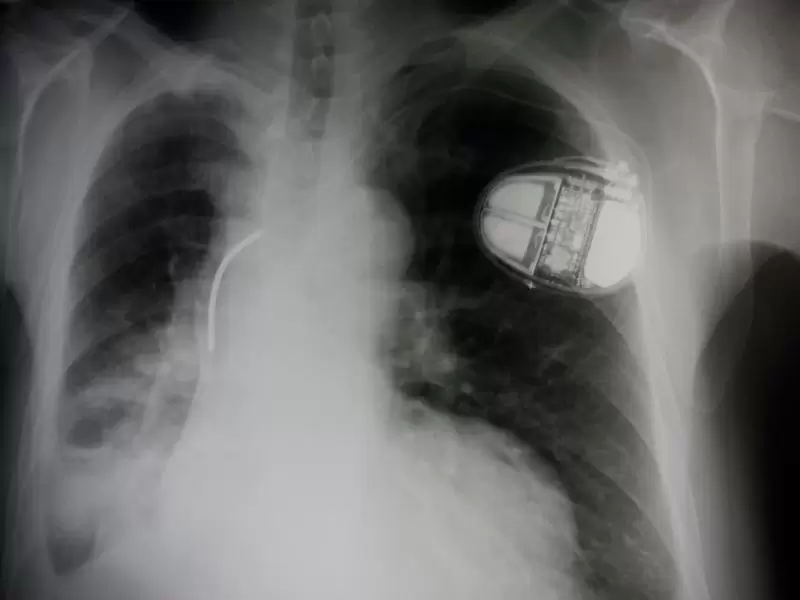

Kalp Pilleri

Bu ileri teknoloji ürünü küçük cihazlar, kalp hızının yavaşlamasını engellemekten kal…